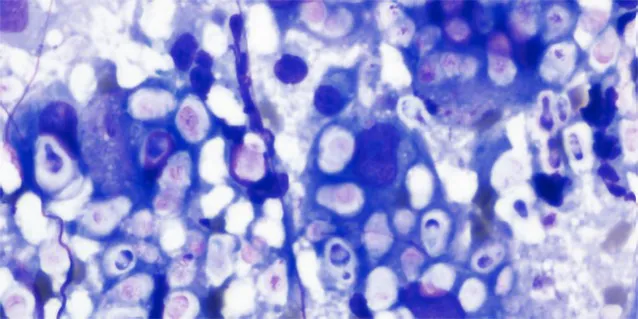

从猫面部皮肤肿块的细针抽吸物中发现隐球酵母。请注意狭窄的芽殖酵母和大而透明的荚膜。

电子显微镜下的隐球菌外观